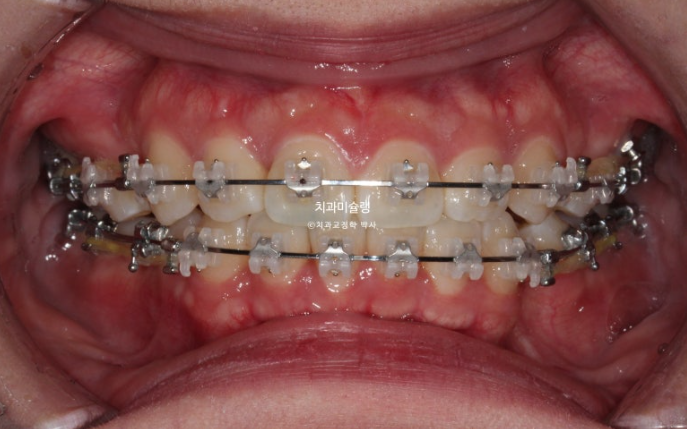

24.08

치료 후 1년째 사진입니다.

발치공간을 없애는 중입니다.

과개교합 개선을 위해 바이트블럭도 설치하고